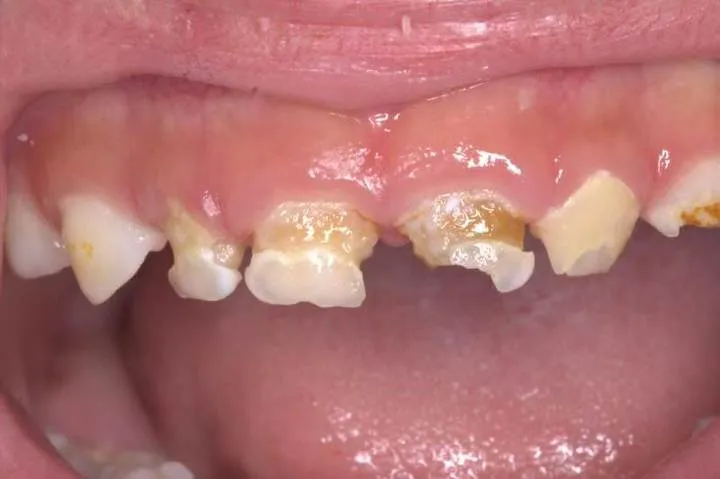

1.大麵積齲壞:齲損涉(shè)及兩個及以上牙麵,剩餘牙體不足50%。

2.牙髓治療後保護:根(gēn)管治療後的乳牙脆弱易折,預成冠可(kě)延長牙齒留存時間。

3.發育缺陷修複:如釉(yòu)質發育不全、遺傳性牙本質疾病導致(zhì)的牙體缺損。

5.外傷牙修複:乳牙冠折露髓或複雜冠根折的保守治療選擇。